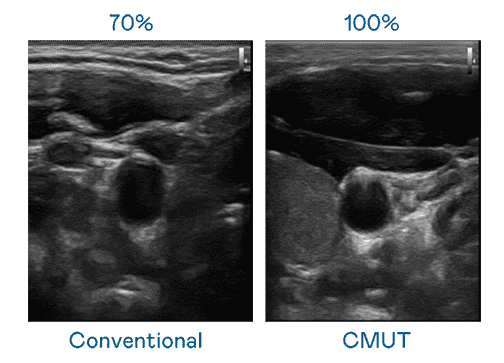

CMUT 技术是一种用电容式微机电元件来产生超音波讯号的技术。。。。与传统 PZT 压电式技术相比,,,,CMUT 频宽增加 30%,,,更宽频的超音波讯号让影像解析度大幅提升,,,,是实现高影像品质医疗超音波扫描、、、、促进精准医疗发展的关键技术。。

大频宽带来超清晰影像

超音波影像的解析度高低,,,,首先取决于探头能发出的讯号频宽。。。传奇国际 CMUT 可提供高清晰的超音波讯号,,提供高频宽、、、高灵敏度、、、、影像纹理细节更高的超音波影像,,协助医护人员缩短影像判读时间及利用精准的医疗影像进行诊断。。